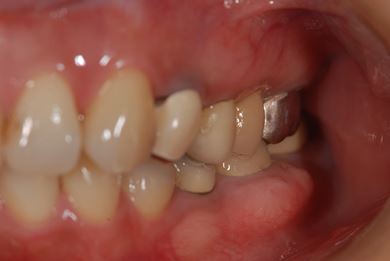

| 性別/年齢 | 女性 / 46歳 | ||||||||||||||||||||||||||||||||

| 主訴 | 上の前歯をセラミックにしたい。 | ||||||||||||||||||||||||||||||||

| 治療内容 | メタルボンドセラミックブリッジ3本(メタルボンドセラミック用土台1本)、オールセラミック5本(オールセラミック用土台4本)、オールセラミックラミネートベニア2本 | ||||||||||||||||||||||||||||||||

| 治療期間 | 9ヶ月 |